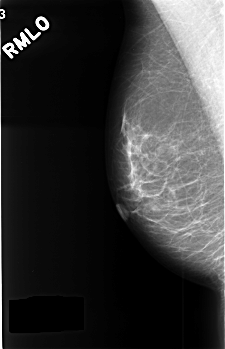

C_0388_1.RIGHT_MLO

RIGHT_CC LINES 4528 PIXELS_PER_LINE 2920 BITS_PER_PIXEL 12 RESOLUTION 50 NON_OVERLAY

RIGHT_MLO LINES 4536 PIXELS_PER_LINE 2920 BITS_PER_PIXEL 12 RESOLUTION 50 NON_OVERLAY